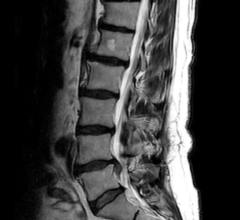

The world of medical imaging is marking a significant milestone in 2023: the 50th anniversary of magnetic resonance ...